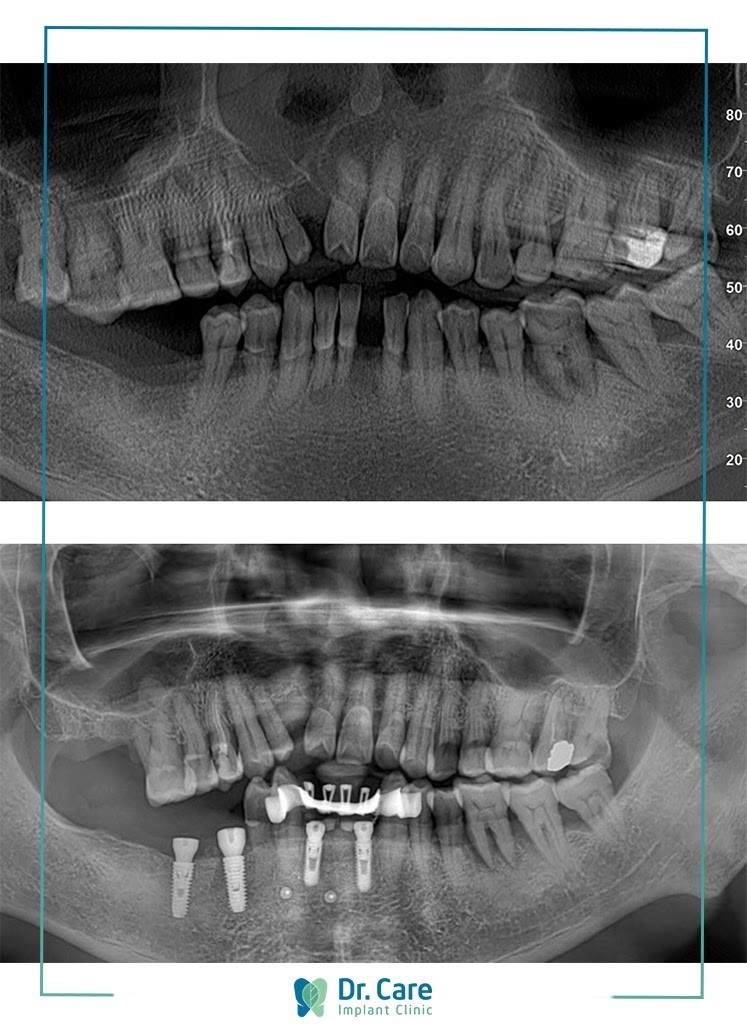

Dr. Care anh 3

Hình ảnh trước và sau khi trồng răng Implant của chú Định.